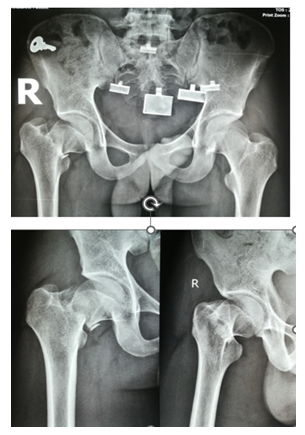

After selecting a case according to inclusion and exclusion criteria, patients were evaluated preoperatively. An elaborate history was taken. This was followed by a general examination and local examination. After admission, patients were put on surface traction to the affected limb with 1/10th of the patient's body weight. All patients underwent preoperative counselling regarding the operative procedure, probable complications, outcome, and other treatment options, along with their merits and demerits. After being informed, written consent was obtained. After preparing the patients for operation, Closed reduction is performed with the patient in the supine position on a fracture table (Figure 1). Reduction was confirmed by C-arm. After reduction, three guide wires are placed, usually in an inverted triangular fashion (Figure 2).